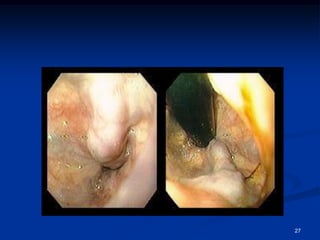

LA FIBROSCOPIE (FOGD)

les varices oesophagiennes: cordons bleutés de taille

variable, au niveau du 1/3 inférieur de l’œsophage:

- grade 1: petites VO (- 5mm) disparaissant à

l’insufflation

- grade 2: grosses VO (+ 5mm) non confluentes, ne

disparaissant pas à l’insufflation

- grade 3: grosses varices confluentes permanentes

26